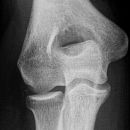

Radiusköpfchen

Qualitätskriterien

Orthograde, überlagerungsfreie Abbildung des Radiusköpfchen, freie Darstellung der Articulatio humero-ulnaris